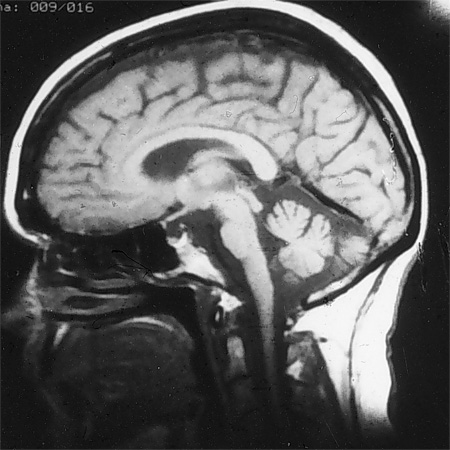

Investigations include an MRI of the brain, which excludes structural lesions and documents cerebellar atrophy with or without brain stem or upper spinal cord atrophy.[32] Thyroid studies, vitamin levels (i.e., B1, B6, B12), methylmalonic acid and homocysteine levels (which indicate B12 status), drug levels (e.g., phenytoin, carbamazepine, phenobarbital as indicated), antibodies to glutamic acid decarboxylase, gliadin, and endomysium (tissue transglutaminase), parietal cell antibodies, paraneoplastic antibodies, HIV serology, polymerase chain reaction for Whipple's disease, monoclonal spike studies (such as serum immunoelectrophoresis), anti-MAG antibodies, intestinal biopsy, and peripheral nerve electrophysiology may all contribute to the diagnosis. Specific tests should be selected based on clinical information.[Figure caption and citation for the preceding image starts]: MRI of brain showing early cerebellar and brain stem atrophy in SCA 1From the collection of Dr S. H. Subramony; used with permission [Citation ends].